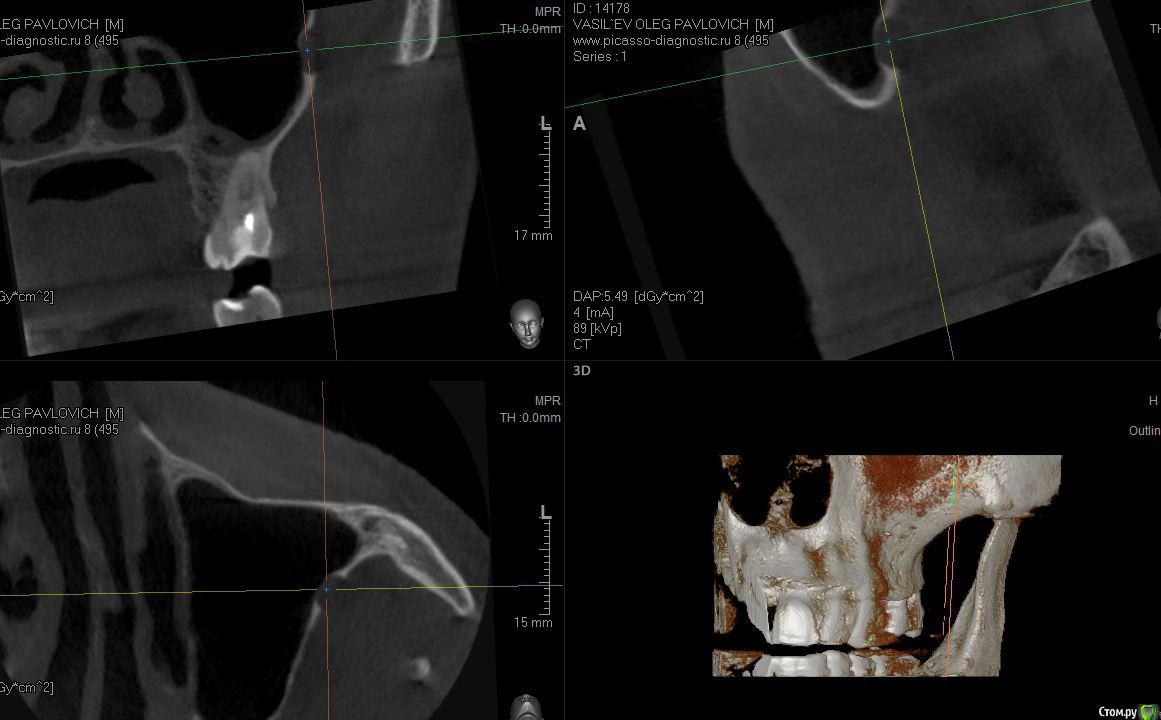

sugaka30 Опубликовано 7 января, 2017 Автор Поделиться Опубликовано 7 января, 2017 (изменено) Сделал Кт Может кто прокоментирует Не пора ли мне Пора? А то что то мне все плохеет https://yadi.sk/d/RXxAPdk237XVpi Заранее спасибо Изменено 7 января, 2017 пользователем sugaka30 Ссылка на комментарий

sugaka30 Опубликовано 7 января, 2017 Автор Поделиться Опубликовано 7 января, 2017 И скажите все таки есть перфо материала в гайморову или пронесло? Ссылка на комментарий

sugaka30 Опубликовано 22 января, 2017 Автор Поделиться Опубликовано 22 января, 2017 Проконсультируйте пожалуйста по этим срезам А то местный хирург не может понять что не так Ссылка на комментарий

red_butler Опубликовано 22 января, 2017 Поделиться Опубликовано 22 января, 2017 ЛОР не оперировал данную область? Ссылка на комментарий

sugaka30 Опубликовано 22 января, 2017 Автор Поделиться Опубликовано 22 января, 2017 (изменено) Я к лору еще не обращался . И до проблемы с зубом Челюсть не ломал и никакого дискомфорта не испытывал На данный момент при нажатии на сам зуб болей никаких нет а вот При надавливании пальцем на кость между щекой и зубом в направлении скулы - нытье и под вечер кратковременная боль отдающая в ухо Может это от 7 ки ?Ну и постоянная сухость во рту Может еще и печень подсадил Пил в течении этих полутора месяцев 2 ципролета - 10 таблеток Диклофенак -3 и Нимесулид-3 А что это за Область? И что в ней не так? Изменено 22 января, 2017 пользователем sugaka30 Ссылка на комментарий

St. Опубликовано 22 января, 2017 Поделиться Опубликовано 22 января, 2017 Скрины кт в обл леченного зуба Ссылка на комментарий